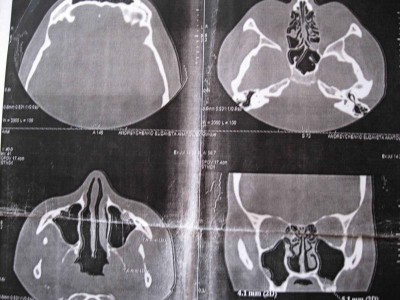

КТ выкладываю. Там разрастание слизистой в решетках и киста в гайморовой пазухе.

Разрастание слизистой в решетках

У Вас типичные симптомы хронического этмоидита в стадии декомпенсации, Вам необходимо пройти обязательный курс антибиотикотерапии. Насчет кист-операция проводится только вне обострений всех заболеваний пазух и только при наличии показаний.